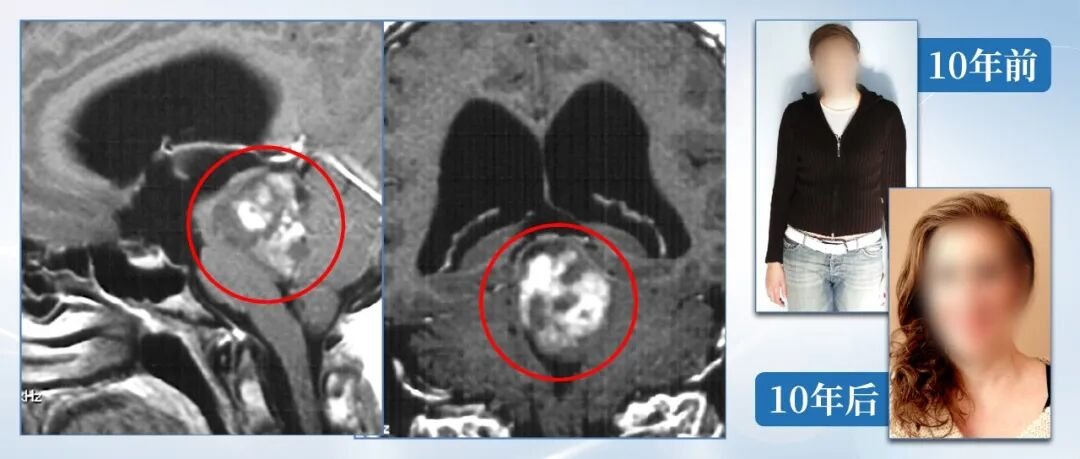

案例二:中脑胶质瘤,术后10年未复发

患者为28岁脑干胶质瘤男性,曾在外院接受两次手术探查,仅做了肿瘤活检,病理报告为毛细胞型星形细胞瘤(WHO I级)。因肿瘤持续增大,患者先后接受了外院建议的放射治疗及为期12个月的替莫唑胺化疗,但疗效均不理想。巴特朗菲教授为其完成肿瘤全切手术后,随访10年未见复发。